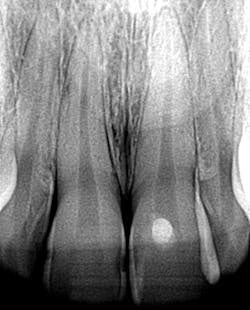

A 26-YEAR-OLD FEMALE PRESENTS for a new-patient exam. She had already been seen for a limited exam and subsequent extraction of a wisdom tooth. She was diagnosed with generalized Class II periodontal disease and multiple restorative needs, including gross apple-core and interproximal caries. It is highly likely that several teeth will end up needing crowns and possible root canals. However, due to the extent of perio, the immediate goal is to stabilize and arrest the caries. Restoring form and function will soon follow. See Figures 1 and 2.

I took a generalized glance in her mouth and, yup, gross caries was everywhere. Still. And the patient is in Invisalign aligners. That dark tooth in the front didn’t just get there for no reason.

In this case, the orthodontist and I were able to stand together and paint a scenario that in the end was much more appealing to the patient. No matter how many aligners she puts in her mouth, that dark tooth in the front won’t go away on its own, and, in fact, it will supersede the beauty of her straight teeth every single time she smiles.